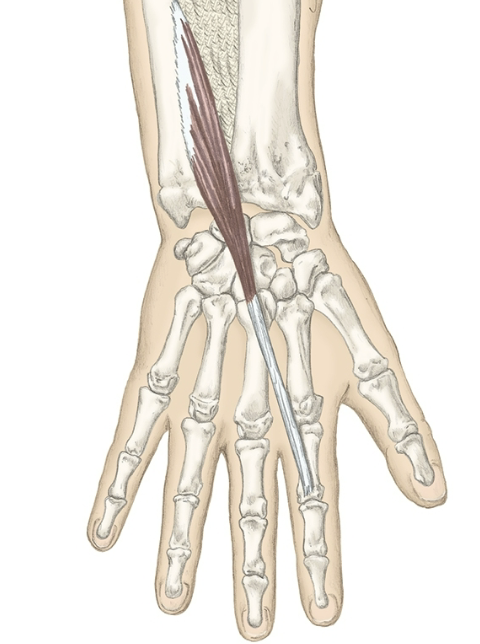

Action of Flexor Digitorum Profundus

Flexion of 2-5 fingers [ MCP,PIP,DIP]

Origin of Flexor Digitorum Profundus

Proximal ulna and anterior, and medial

Insertion of Flexor Digitorum Profundus

Base of palmar surface of distal phalanges 2-5

Nerve that the Flexor Digitorum Profundus innervates

Median Nerve